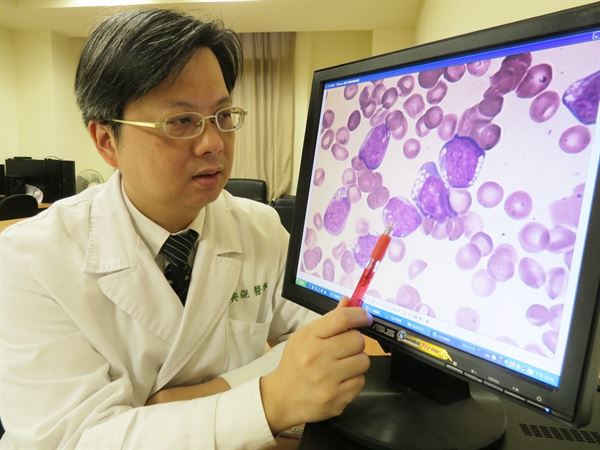

對此,台中慈濟醫院血液腫瘤科主任李典錕醫師表示,該名男子之所以罹患血癌,主要是因為「基因突變造成」,不過血癌並非完全無藥可治,且治癒成功率高達七成,於是開始為李姓男子進行化療。